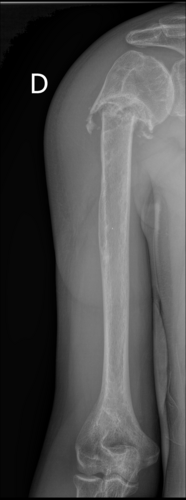

Meu namorado foi atingido por uma carro em 2020 e fraturou o úmero superior direito, fez cirurgia e colocou fios de Kirschner, fez fisioterapia mas nunca chegou a ficar 100%. Perdendo 75% da movimentação do braço! Após novo trauma no braço descobriu que a fratura nunca colou / nunca se consolidou, criando pseudoartrose, agora precisando fazer uma nova cirurgia e por uma placa, algo que não é contemplado pelo SUS / Sistema Único de Saúde. Ele não consegue trabalhar e se manter, sente dor e a movimentação está menor do que antes! O mesmo precisará entrar na justiça, sabemos como isso é demorado. Então pretendemos fazer particular. A cirurgia tem um custo estimado em 30 mil reais! Toda ajuda será bem vinda!

Cid M84.1